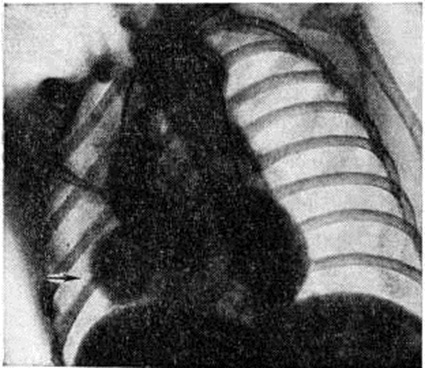

Рентгенограмма грудной клетки больного при полной форме атриовентрикулярного канала (прямая проекция): контуры сердца округлой формы за счёт увеличения правых и левых отделов.

Определяемое расщепление II тона с усилением лёгочного компонента связано с гиперволемией малого круга и блокадой правой ножки пучка Гиса. На ЭКГ — отклонение электрической оси сердца влево. На ФКГ над верхушкой сердца и в четвёртом межреберье слева регистрируется интенсивный систолический шум, связанный с регургитацией крови из желудочков и сбросом крови из левого желудочка в правый. Эхокардиограмма регистрирует необычные движения передней створки митрального клапана, иногда её расщепление и наличие промежутка между ней и межжелудочковой перегородкой. Рентгенологически определяется умеренная или значительная кардиомегалия и дилатация лёгочного ствола (рисунок 7).